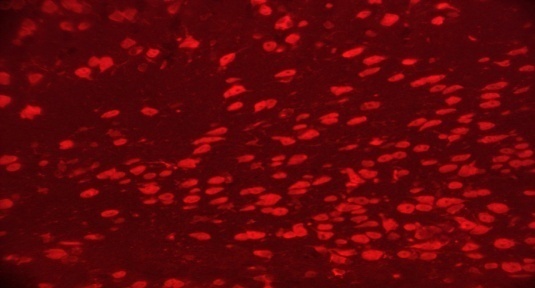

TEL increased NeuN expressions in MPTP intoxicated mice brain

SNpc and ST regions of MPTP mice brain showed a significant decrease in % NeuN immunopositive cells [F (4,10) = 274.1, p<0.01 and F (4,10) = 86.24, p<0.01, respectively] when compared to the vehicle treated mice. TEL (3 and 10 mg/kg) significantly (p<0.01) increased % NeuN immunopositive cells in both the regions in comparison to MPTP mice (fig. 4).

Fig. 4: Effect of TEL on % NeuN immunopositive cells in MPTP intoxicated mice brain. Pictures represent NeuN immunopositive cells of (A) SNPc and (B) ST brain regions X 400 magnification. (1) Normal control, (2) MPTP induced mice brain, (3) TEL (3 mg/kg b. wt.) administered MPTP mice brain, (4) TEL (10 mg/kg b. wt.) administered MPTP mice brain and (5) TEL (10 mg/kg b. wt.) administered normal mice brain. (C) Values were expressed in mean±SEM, n=4 animals/group, statistical analysis was performed using one way ANOVA followed by Tukey’s multiple comparison test, ## indicates p value<0.01 Vs group I, ** indicates p value<0.01 Vs group II